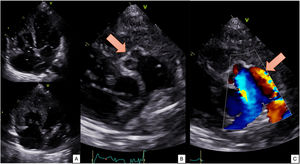

- Congestión refractaria tras pericardiocentesis efectiva en un taponamiento cardiaco: pericarditis efusivoconstrictiva por Cutibacterium acnes

- Meritxell Santaló-Corcoy, Laura Triguero-Llonch, Juan Fernández-Martínez, Jessica P. Arias-Pinilla, Miguel Ferrer-Menéndez, Ana Bonet-Basiero

- Rev Esp Cardiol. 2025;78:1004-6